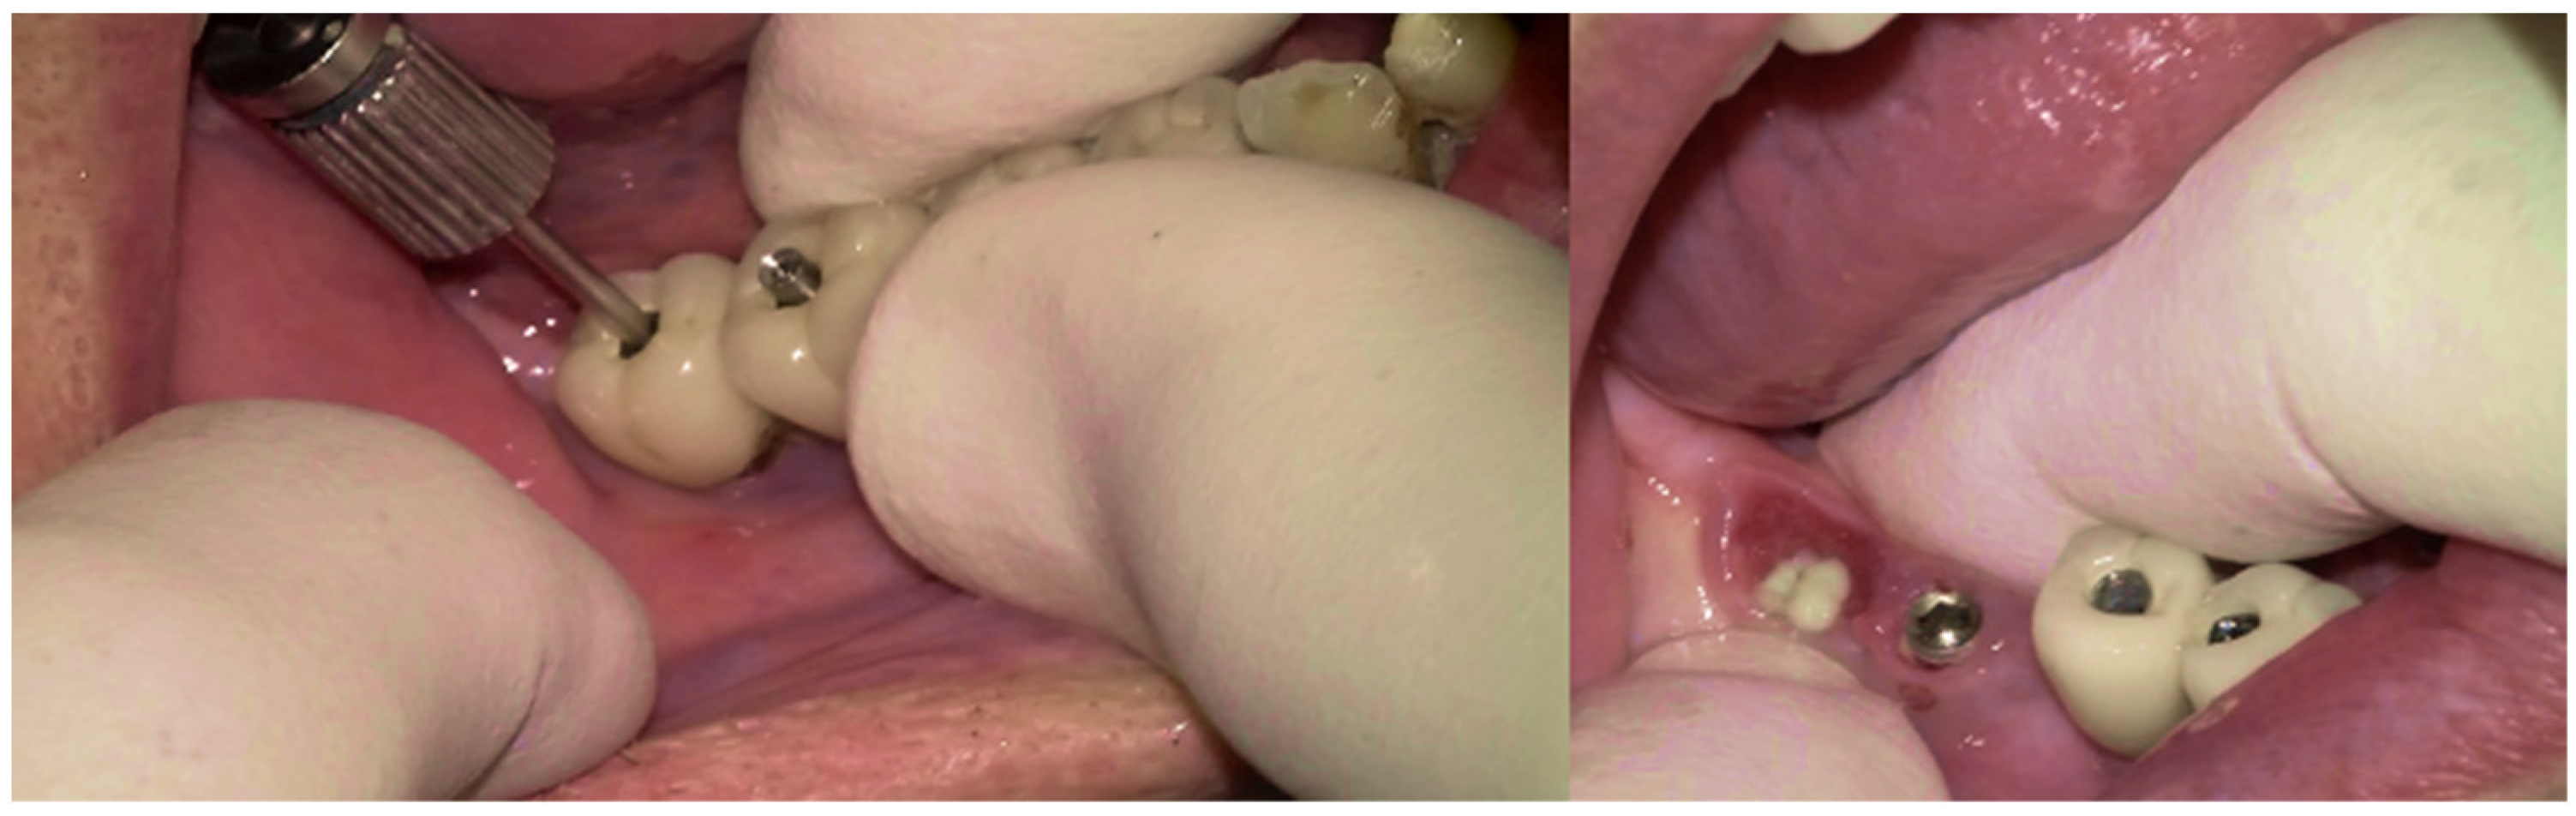

The same protocol mentioned above was used. A five-day antibiotic regimen was administered prior to the surgical procedure. At the surgery, the site had no suppuration and minimal BoP; the implants #33, #36, #37, #44, and #47 were removed, and new implants were placed to provide a new rehabilitation. For the site #41 (without mobility and severe bone loss), following prosthesis and abutment removal (Figure 17a,b), a BSF with two crestal extensions was made around the implants (Figure 17c,d), facilitating optimal access and flap management during the surgical procedure, eliminating the need to retract two flaps, as a midcrestal flap requires. The flap was retracted lingually; the granulation tissue was removed, and the contaminated implant surface fully exposed (Figure 17d).

The specialized “pin” guide was attached to the implant and contacts in juxtaposition with the surface of the implant–abutment connection platform (Figure 17e,f). The guide, extending the long axis of the implant, was used to position and control the iMPACT device’s rotational movement (Figure 17g,h), with cutting blades extended to maximum capacity (Figure 17h,i). Initial rotation levels of the alveolar bone (Figure 17j,k) permitted controlled mechanical injury to the bone, initiating the bone healing response, known as “Bone Regeneration Induction,” which is the second principle of the “Quadrant protocol.” Incremental machining at speeds between 200–300 RPM with torque settings of 7–9 N·cm removed contaminated implant threads (Figure 17l). The cutting action of the iMPACT prevents heating during manipulation, and the suction airflow removes macroparticles without the need for irrigation; thus, producing macro-sized particles removed via suction. The non-irrigation approach established an oxidative environment conducive to passivation layer formation. Post-machining (Figure 17l), the site was thoroughly cleaned and dried, and bleeding was stimulated and associated with the bone particulate graft (Figure 17m). The flap was repositioned, and abutments were placed back to keep and hold it in position for the final suture (Figure 17n). Antibiotics were continued postoperatively for three additional days.

Figure 17. Step-by-step treatment for peri-implantitis using the iMPACT and Quadrant protocol. (a) Initial clinical evaluation; (b) Removing the abutments for peri-implantitis treatment; (c,d) BSF raised for implant exposition; (e) Insertion of the hinge (pin), which was crewed into the implant; (f) Hinge in position; (g,h) iMPACT adapted to the hinge; (i) iMPACT spinning for implantoplasty; (j) The implant surface was smoothed, and bone around the implant was gently cut (osteotomy); (k) occlusal view showing the osteotomy; (l) implantoplasty finished—implant surface is completely smoothed (machined); (m) Bone graft; (n) Suture and abutments were repositioned.